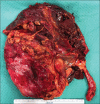

A 85-year-old female patient underwent nephrostomy tube insertion for a huge hydronephrosis due to a papillary mass involving the right ureteral ostium diagnosed by at computed tomography scan. As soon as the nephrostomy tube was inserted, a pulsatile bleeding was found and a renal angiography was done. A massive bleeding from the main and unique right renal artery was found such as to require prompt endovascular embolization. A transurethral resection of the bladder was performed and the pathology report confirmed high-grade pTa transitional cell carcinoma. An open drainage was then placed to empty the contents of the pyelocalyceal system of the kidney. Once obtained the volumetric reduction of the abdominal mass the patient underwent the right nephroureterectomy.